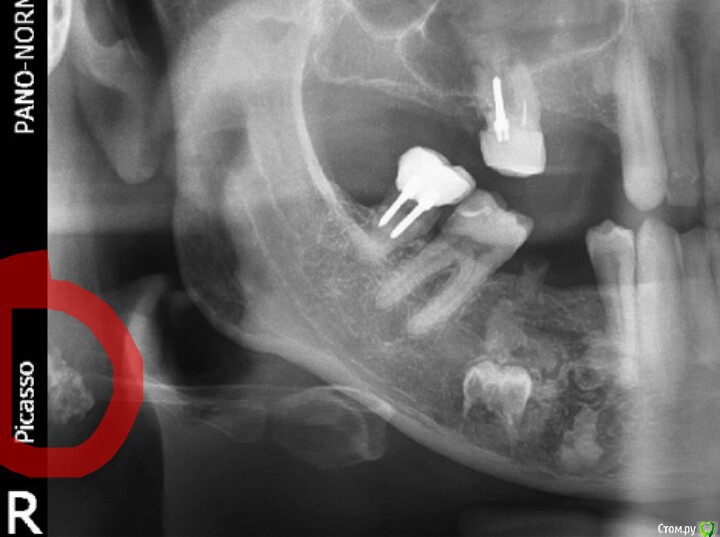

vse32 Опубликовано 11 марта, 2019 Поделиться Опубликовано 11 марта, 2019 (изменено) Нужна консультация. Что эта за штука в 4 сегменте? Снимок от 2016 года, корешок то ли 45, то ли 46 удален год назад. Симптоматики никакой нет. Обнаружено случайно по снимку. Пациенту 58 лет, мужчина.Собственно, основной вопрос: что это такое и чем может грозить? И надо ли с этим что-то делать?В случае имплантации - вероятно надо. В случае мостовидного протеза?Я предположила, что это киста с зачатком. Изменено 11 марта, 2019 пользователем vse32 Ссылка на комментарий

Kolchanov Опубликовано 11 марта, 2019 Поделиться Опубликовано 11 марта, 2019 На одонтому похоже. Ссылка на комментарий

Дмитрий Л. Опубликовано 11 марта, 2019 Поделиться Опубликовано 11 марта, 2019 Да, составная одонтома, можно на биопсию отправить. Полное удаление будет инвазивным, я бы мост предложил. Ссылка на комментарий

Дмитрий Л. Опубликовано 11 марта, 2019 Поделиться Опубликовано 11 марта, 2019 Расспросите про почки. Направьте к урологу\нефрологу и кардиологу, на скриншоте отметил возможный участок кальцификации.Ds. - каротидный атеросклероз - ? 3 Ссылка на комментарий